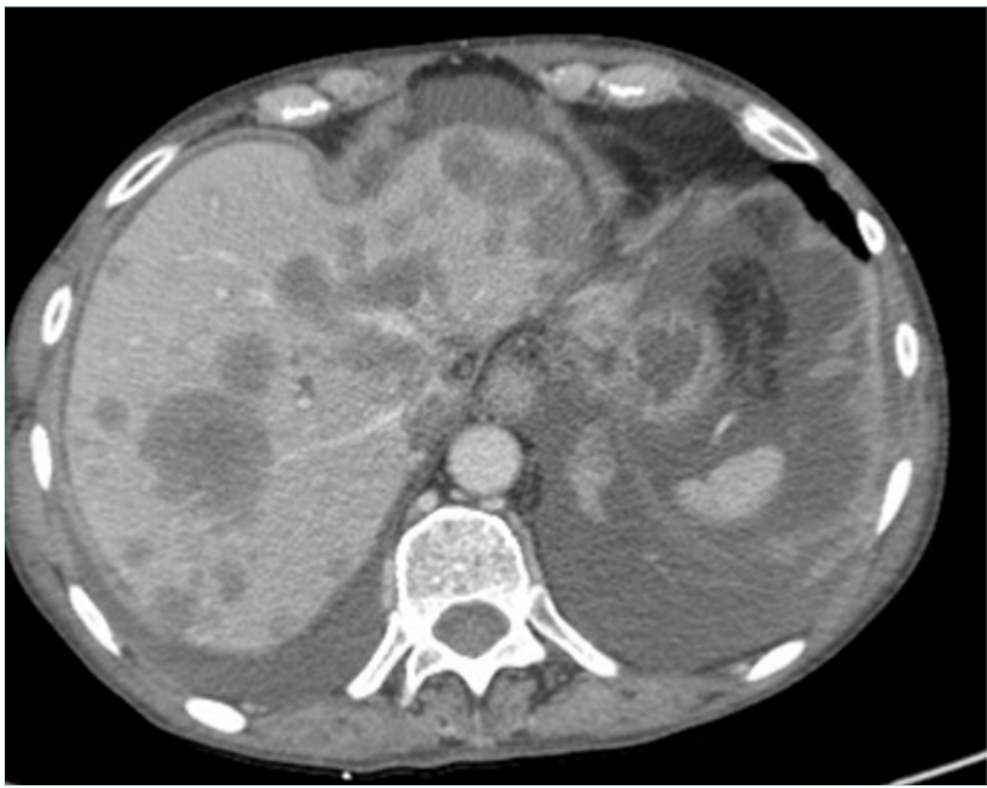

In these patients, prognosis mainly relies on the oncologic status and can be excellent when the cancer is cured (Figure 5). Therefore, results of stenting in terms of clinical outcome and patency rates should be comparable to nonmalignant lesions.

Figure 5. 44-year-old man suffering from symptomatic inferior vena cava (IVC) (lower-limb edema) occlusion due to retroperitoneal fibrosis occurring after liver tumor resection: A) IVC occlusion; B) result after recanalization and stenting with 2 Wallstents of 16 mm in diameter. Patient remained asymptomatic at 108 months of follow-up.

Literature is very scarce on this specific topic, and reports focus mainly on complications of the iliac veins but some cases are certainly included in series on venous stenting for active cancer. Brechtel reported 1 case of anastomotic stenosis after surgical bypass on the IVC during reconstruction for hepatic tumor that was successfully treated by stenting.30 Murakami reported 1 case of retroperitoneal fibrosis after radiotherapy for uterine cervical cancer with good result after IVC stenting.31 In our experience, we treated 7 patients with late complications of cancer treatment (2 postoperative retroperitoneal fibrosis, 3 had previous lymph node resection and subsequent radiotherapy, 1 radiotherapy, 1 anastomotic stenosis after surgical IVC reconstruction for leiomyosarcoma). All had successful stenting and secondary patency was 100% after a mean 81-month follow-up (26-212 months).